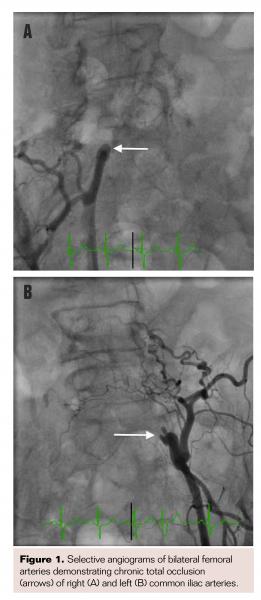

Urgent cardiac catheterization was performed via a right femoral arterial approach. The access wire could not be advanced beyond the right external iliac artery and selective angiogram revealed complete occlusion of the right common iliac artery (CIA) (Figure 1A). Access was then obtained in the left common femoral artery (CFA) with similar results confirming complete occlusion of the left CIA (Figure 1B).